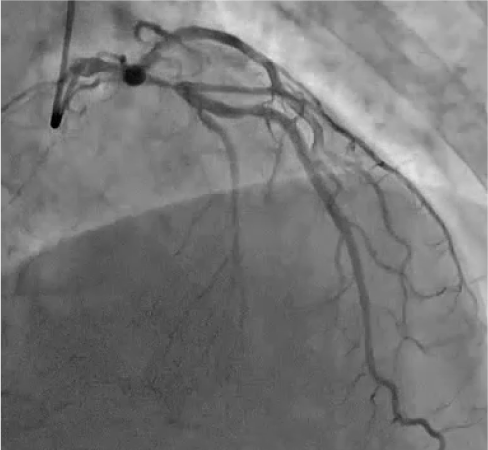

LCA CAG

-